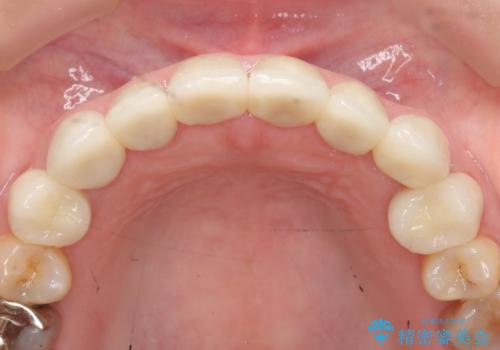

上顎は左側 4 番目から右側 4 番目までの 8 歯をオールセラミッククラウンで補綴しました。

今回用いたオールセラミッククラウンはジルコニアフレームという白い素材の上にセラミックを盛っているため、審美性が非常に高いのが特徴です。

また、ジルコニアは人工ダイヤモンドの材料にも使われているほど高い強度を持っており、そのためオールセラミッククラウンは審美性だけでなく、奥歯やブリッジの補綴も可能とするクラウンです。